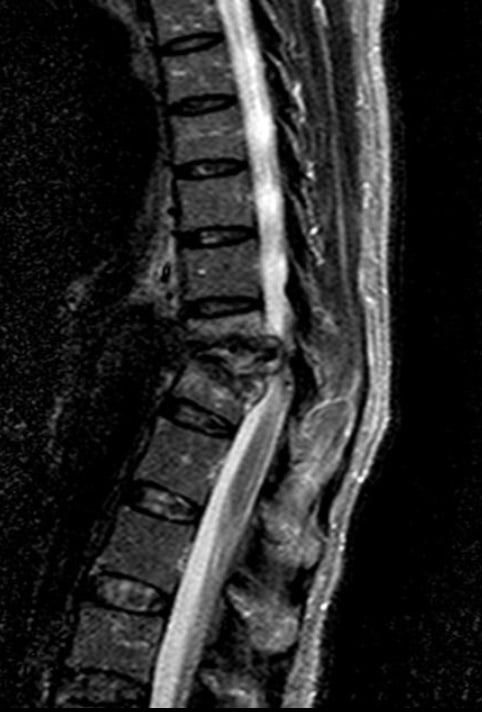

- Hình ảnh cắt ngang cho phép đánh giá tốt hơn mức độ ảnh hưởng và đặc biệt là tổn thương lan vào ống tuỷ, gây chèn ép tuỷ. MRI là thăm dò hình ảnh được lựa chọn cho mục đích này. CT ít nhạy hơn so với MRI.

- Chụp cộng hưởng từ với gadolinium cho phép bác sĩ kiểm tra những bất thường ở các mô, đĩa đệm và đốt sống. Từ đó giúp phát hiện tình trạng hủy xương, hoại tử xương, hẹp khe khớp. Đồng thời kiểm tra chèn ép tủy sống, dây thần kinh và áp xe (nếu có).

- Các đặc điểm bao gồm sự không đều của bản tận và cả mặt trước của thân đốt sống, với sự phù nề của tủy xương trên MRI.

- T1: giảm tín hiệu tủy xương ở các đốt sống liền kề

- T2: tăng tín hiệu tủy xương, đĩa đệm, mô mềm nhiễm trùng

- T1 C+ (Gd): tăng cường nhìn rõ hơn tuỷ xương, dưới dây chằng, đĩa đệm, màng cứng

Các hình ảnh sau trích từ CT và MRI của một bệnh nhân lao cột sống.